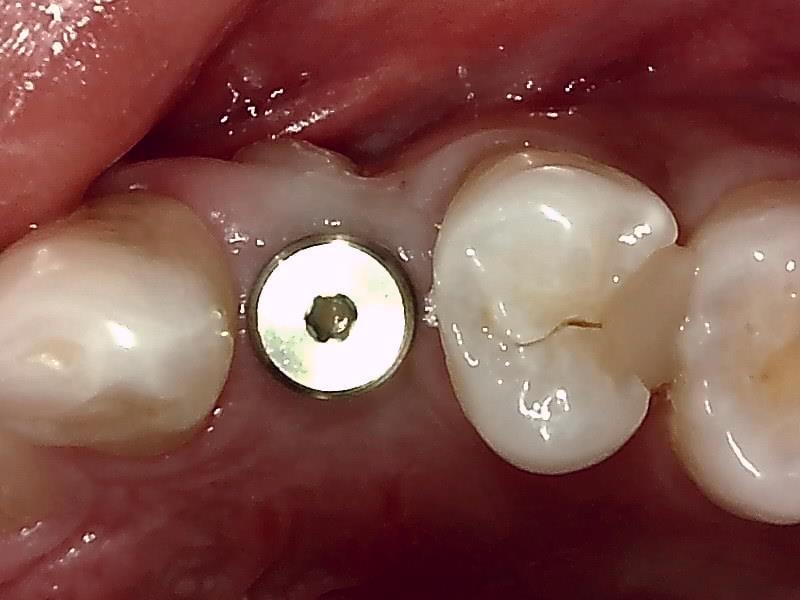

抜糸後

歯肉の整形

術中インプラント埋入したあと、アバットメントの装着のため

歯肉の整形 (左上)とても綺麗な良い歯肉の状態です。